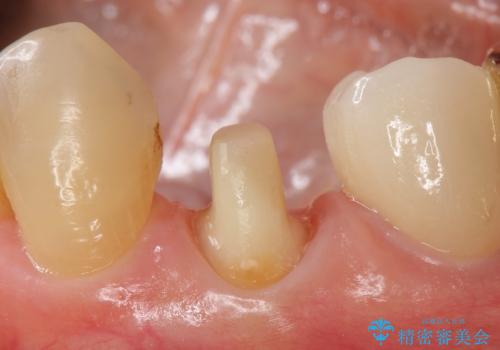

- 左下4番目の歯がなにもしなくてもズキズキ痛むので診て欲しいといらっしゃった方の症例です。

検査の結果、神経の保存は難しかったため、根管治療を行った後オールセラミッククラウンによる補綴を行いました。